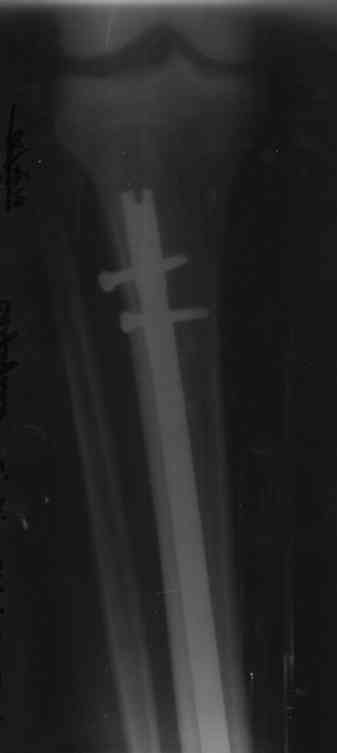

Контрольные снимки перелома через 3 месяца

Добрый день , выкладываю ренген после трех месяцев операции.Появились следующие вопросы:

1.Перелом кости во внутренней части своей по моему мнению не срастается и не сглаживается , из-за этого при разгибании стопы появляется ощущение что данная кость цепляет что-то внутри и начинают неметь большой и второй (следующий) палец на ноге , а в лодыжке боль на 5 минут, потом полностью проходит как и онемение.Надо ли что -то делать(принимать кальций например), или надо просто подождать ?

2.Врач сказал что можно ходить уже без трости(по возможности).Есть ли у меням такая возможность , так как боюсь своего веса 100кг, не до конца срощенного перелома и болей в коленном суставе и суставной щели в разных местах, хотя мышечный тонус думаю мне позволит ходить без опоры или все таки лучше подождать с полной нагрузкой?